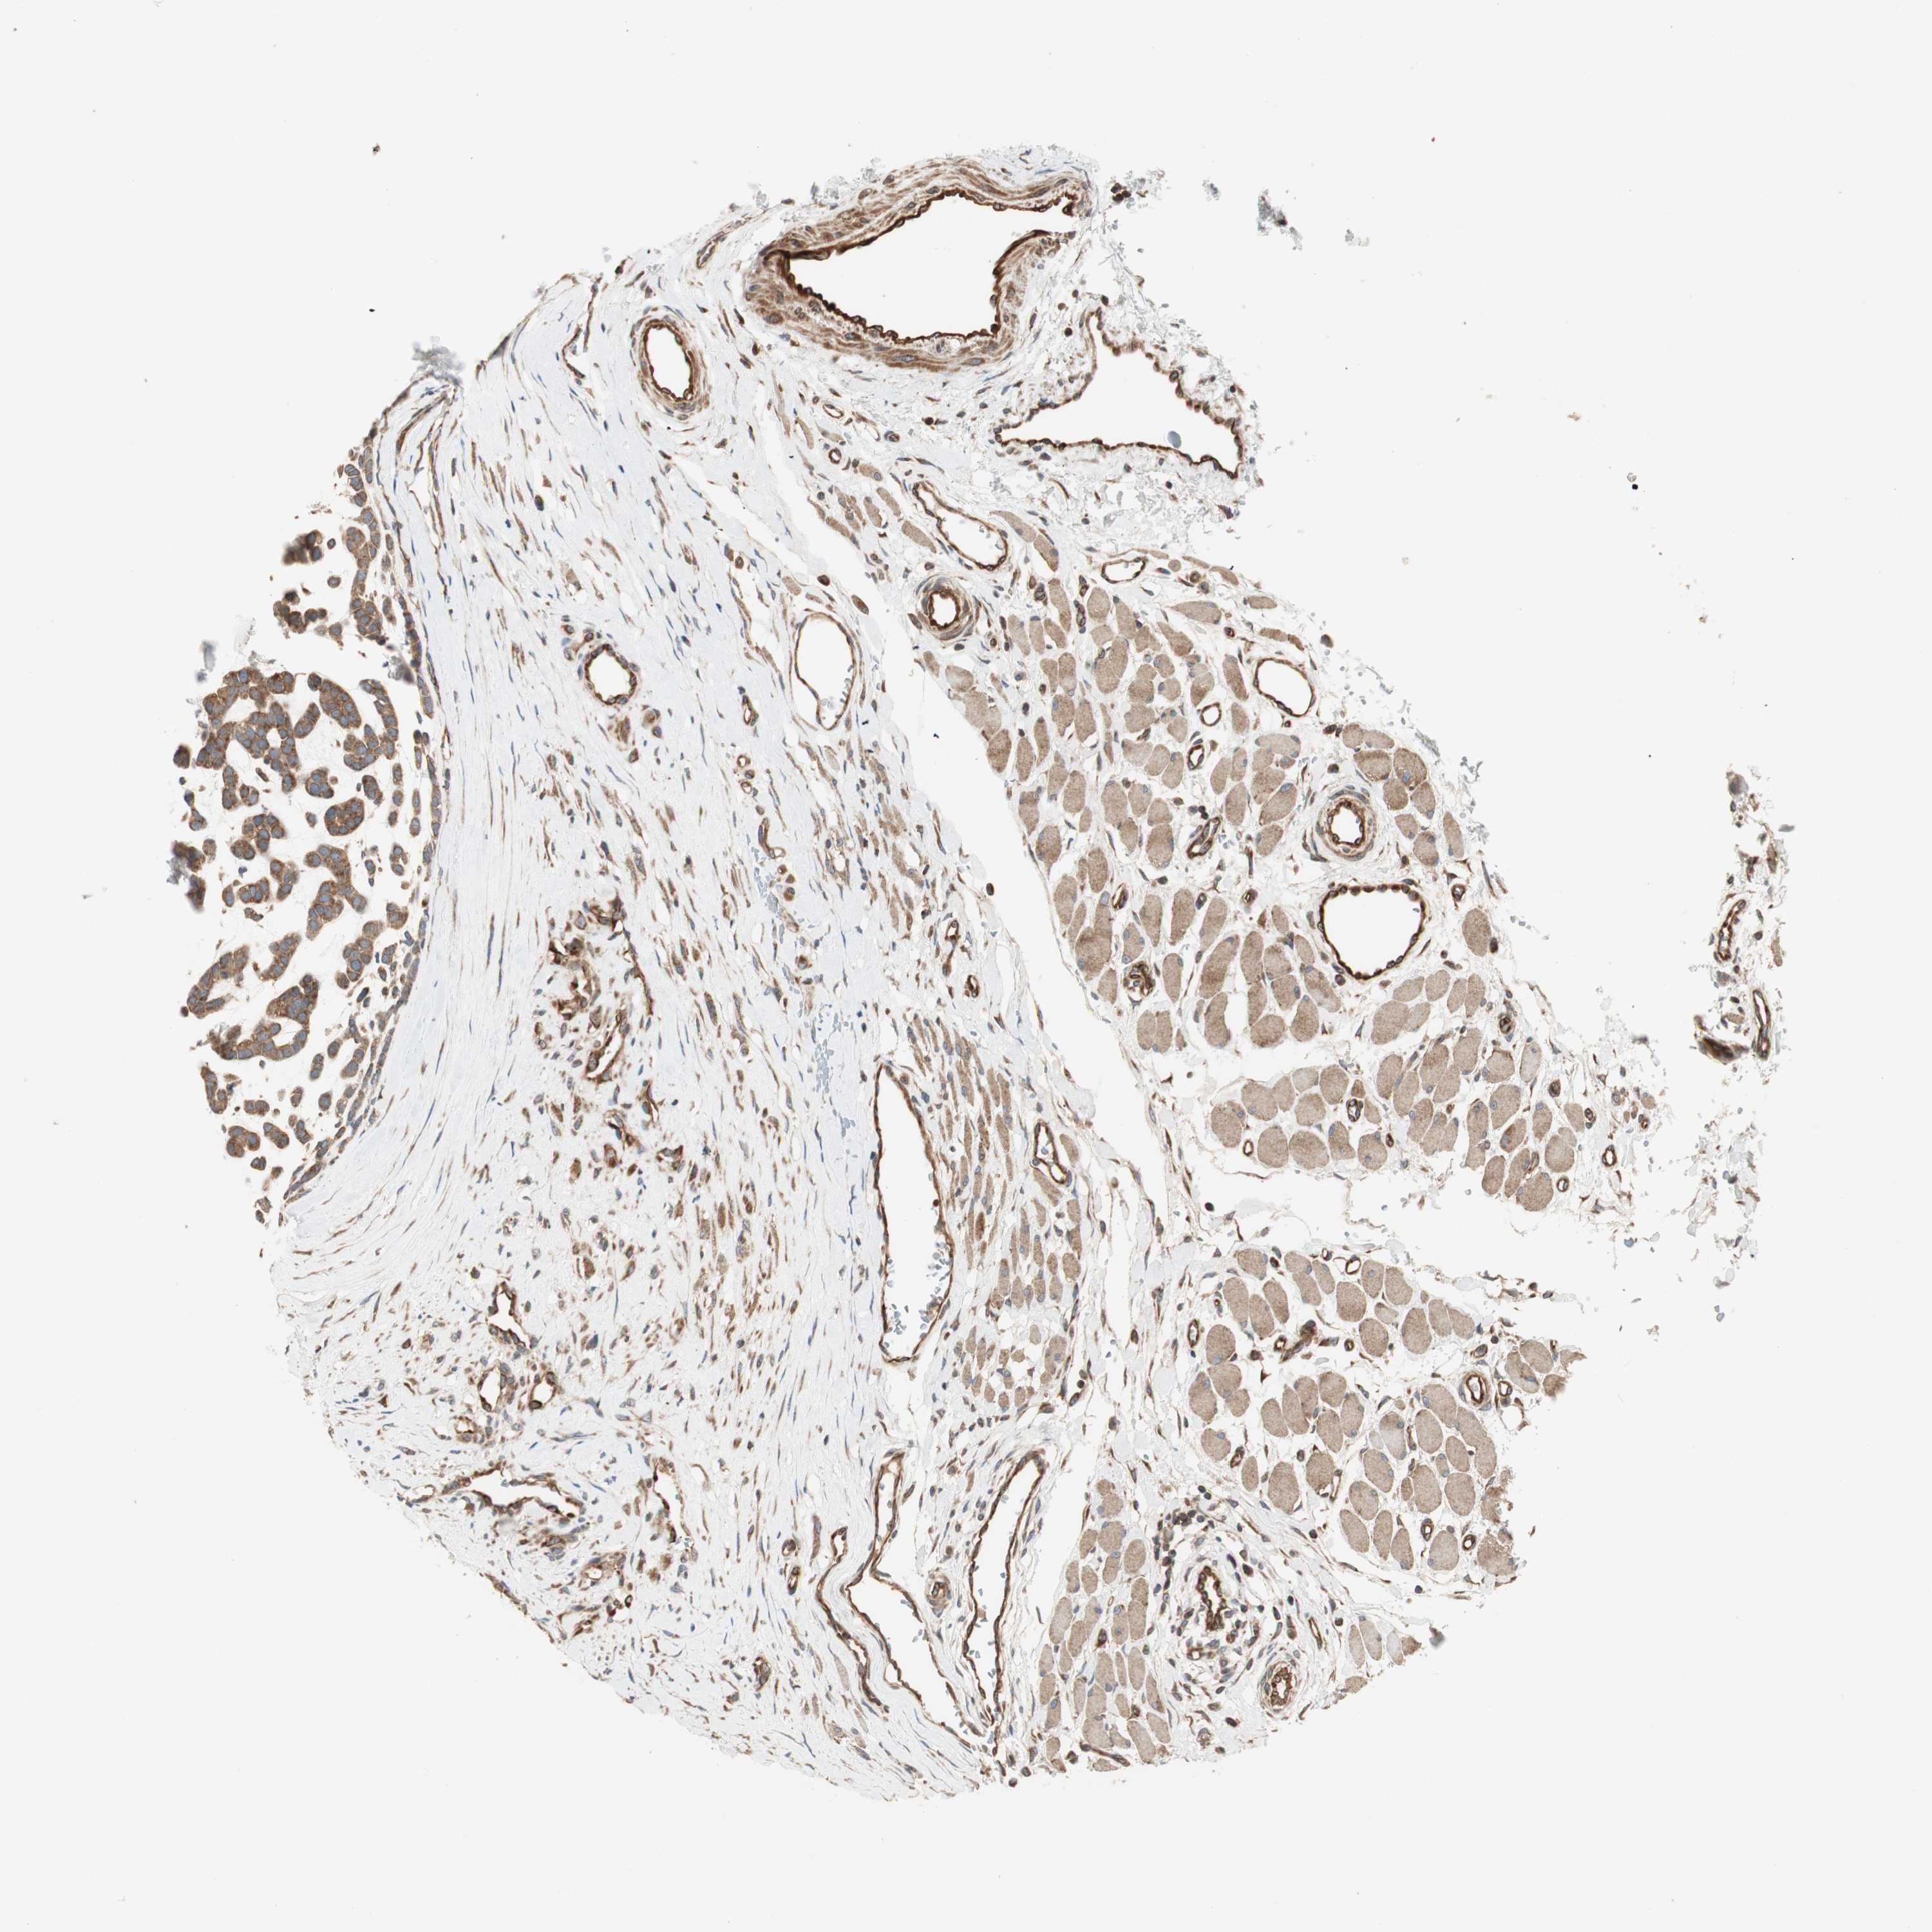

HEAD AND NECK CANCER - Protein expressioni

A mouse-over function shows sample information and annotation data. Click on an image to view it in a full screen mode. Samples can be filtered based on level of antibody staining by selecting one or several of the following categories: high, medium, low and not detected. The assay and annotation is described here.

Antibody stainingi

Antibody staining in the annotated cell types in the current human tissue is reported as not detected, low, medium, or high, based on conventional immunohistochemistry profiling in selected tissues. This score is based on the combination of the staining intensity and fraction of stained cells.

Each image is clickable and will lead to virtual microscopy that enables deeper exploration of all samples and also displays staining intensity scores, fraction scores and subcellular localization as well as patient and tissue information for each sample.

Antibody HPA007301

Staining

High

Medium

Low

Not detected

Intensity

Strong

Moderate

Weak

Negative

Quantity

>75%

75%-25%

<25%

None

Location

Nuclear

Cytoplasmic/membranous

Cytoplasmic/membranous,nuclear

Adenocarcinoma, NOS

Adenoma, NOS